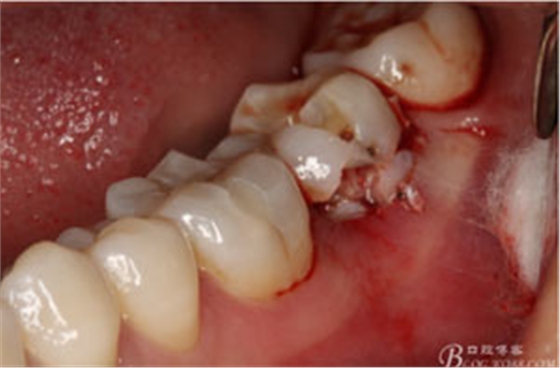

圖6.微創(chuàng)挺拔除37.

圖7.37牙冠碎裂。多生牙壓迫吸收程度嚴重。